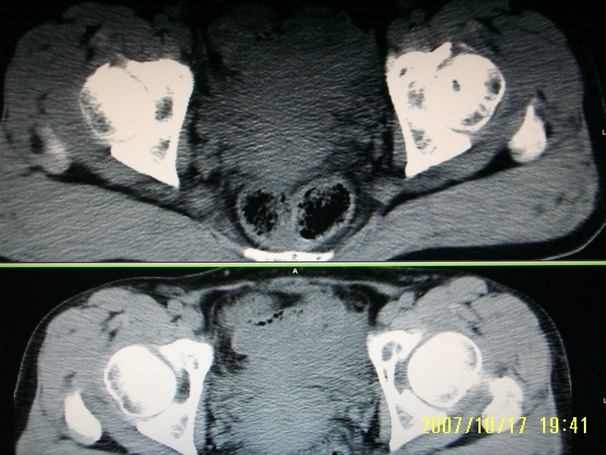

标题: CT10352:女,45岁,股骨头病变,如何诊断? [打印本页]

标题: CT10352:女,45岁,股骨头病变,如何诊断?

股骨头病变,如何诊断?

患者女,45岁,左髋部行走疼痛一年,无外伤史,无感染史。x片示囊状骨透亮区

两侧髋臼结构发育不良伴退行性改变.不除外色素沉着绒毛结节性滑膜炎.

两侧髋臼结构发育不良伴退行性改变

支持成人髋臼发育不良继发髋关节退行性变

髋关节发育不良,左髋关节退变,左髋关节邻关节囊肿

两侧髋臼结构发育不良,做个mr看软骨,必要时换,囊变考虑退变,

双侧股骨头形态都欠规整,外形欠光滑,尤以左侧明显,考虑双侧髋臼发育不良并退行性变